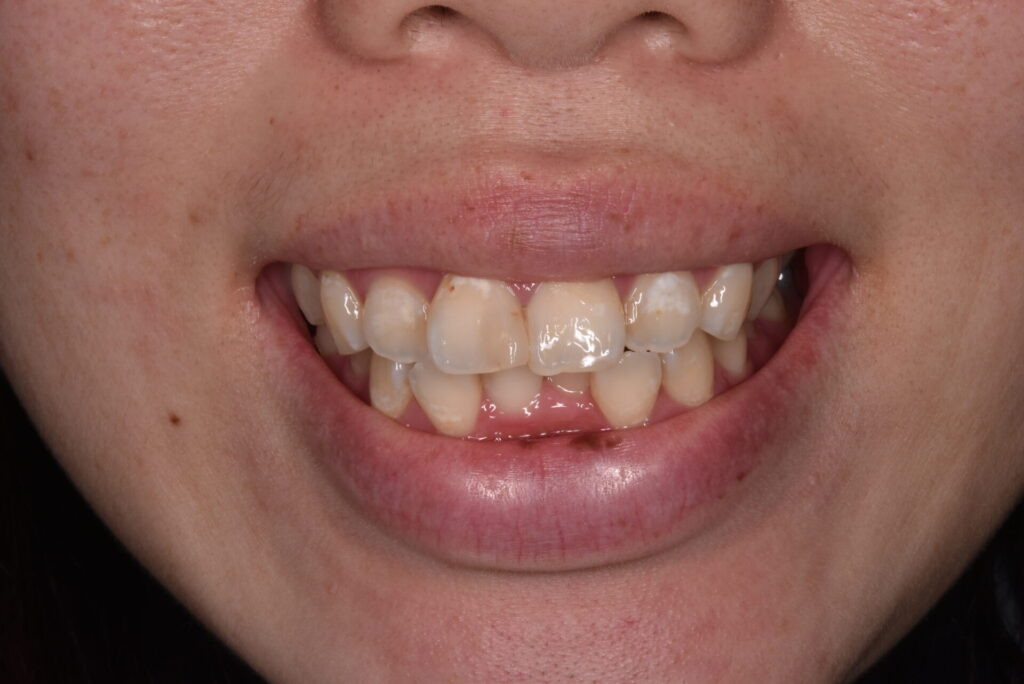

20代女性 滋賀県よりご来院下さいました。主訴は出っ歯感と叢生(乱杭歯:ガタ付きのある歯列 そうせいやらんぐいばと言われます)の改善です。ただ100点の矯正を目指したいわけではなく前歯を中心に改善したいといご希望です。

矯正後

矯正はインビザライン モデレートで行っています。追加アライナーなし 途中妊娠出産のため来院間隔が空いています。